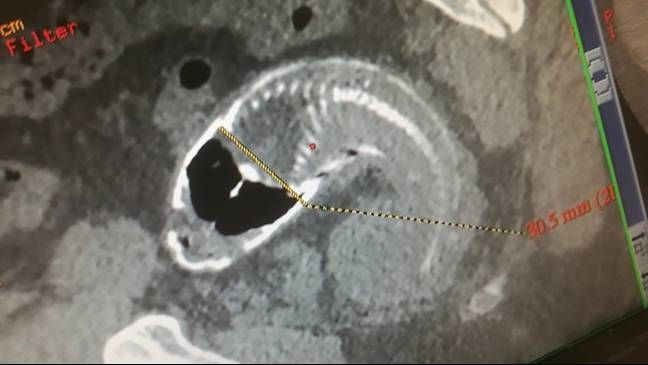

Le scansioni hanno rivelato che l’intero animale è rimasto bloccato all’interno dell’uomo che lamentava un “intenso dolore addominale” durato più di un’ora.

Il pesce (una Tilapia del Mozambico) è stato trovato morto all’interno dell’uomo mentre i medici hanno cercato ripetutamente di farlo uscire. Le pinne spinose hanno anche causato la rottura dell’intestino crasso, il che ha costretto i chirurghi ad aprire l’addome.